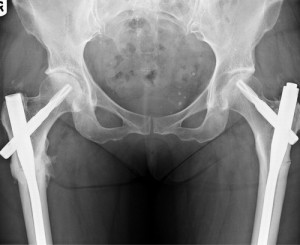

- Травмы верхнего конца бедра. Если произошел перелом верхнего конца кости, метод остеосинтеза не применяется при вколоченных повреждениях шейки бедра. В остальных ситуациях, если позволяют жизненные показания, можно лечить пациента оперативным путем. Часто именно благодаря такому методу можно спасти жизнь пациенту, сократить срок его реабилитации и достичь быстрого сращения перелома. В основном в ходе операции применяются канюлированные винты, г-образная пластина и трехлопастный гвоздь. Остеосинтез выполняется на 2-4 сутки после травмы. Сначала применяют скелетное вытяжение, пациент подготавливается к операции и делается контрольный снимок с помощью рентгена. Целью операции является точное сопоставление костных отломков и их последующая фиксация. Если произошел серединный перелом бедренной шейки, во время операции используется трехлопастный гвоздь.

Перелом бедренного диафиза. В этом случае остеосинтез – главный метод лечения. Консервативный путь выбирается только тогда, когда невозможно использовать хирургическое вмешательство. Операций при переломе диафиза выполняется на 5-7 сутки после травмы. Перед этим накладывается скелетное вытяжение. Во время остеосинтеза применяются пластины, стержни и аппараты для внешней фиксации. Срочную операцию нельзя проводить при тяжелом состоянии пациента. Необходимо сначала нормализовать его состояние. Если перелом оскольчатый или наблюдаются сочетанные травмы, может возникнуть необходимость в срочном обездвиживании отломков, чтобы прекратить последующее травмирование бедренных тканей, так как это может плохо сказаться на состоянии пациента.

Врачи отмечают, что остеосинтез бедра является важной хирургической процедурой, применяемой при различных травмах и заболеваниях. Существует несколько видов остеосинтеза, включая внутренний и внешний. Внутренний остеосинтез подразумевает использование металлических пластин, винтов или стержней, которые фиксируют кости изнутри. Внешний остеосинтез, в свою очередь, включает применение аппаратов, которые крепятся снаружи и обеспечивают стабильность фрагментов кости.

Внешний остеосинтез. При внешнем остеосинтезе бедра чаще возникают специфические осложнения, такие, как развитие контрактур, появления дополнительных фиксационных точек и повреждение сосудисто-нервных пучков спицами. Этот метод используется только по показаниям. Имеются в виду повреждения, при которых проведение внутреннего остеосинтеза чревато тяжелыми осложнениями. Их риск велик при сочетанных, осложненных открытых, огнестрельных, многооскольчатых, закрытых оскольчатых и сегментарных переломах. Такие травмы являются показанием к проведению внешнего остеосинтеза.

Если такая операция выполняется стержневыми или компрессионно-дистракционными аппаратами, это сильно расширяет ее возможности при огнестрельных переломах. В этом случае обеспечивается открытая или закрытая репозиция костных отломков. Получается не только достичь их прочной фиксации, но и сохранить доступ к ране и снизить риск развития раневых инфекционных осложнений в месте повреждения. Сегодня для того чтобы уменьшить недостатки операции ведутся разработки по созданию новых устройств и приемов операции.